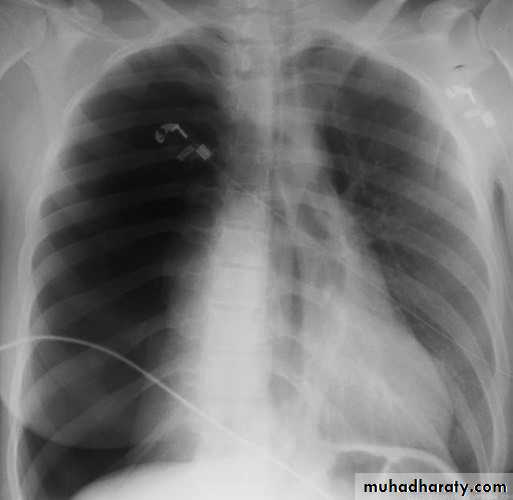

Case 1A 28 years old previously healthy female presented with sudden onset of localized right sided chest pain and feeling of shortness of breath.

OE: looks in pain, RR 22, PR 125. normal BP and Temp.

CXR shown

case 1

The chest X-ray shows thesharply defined edge

of the deflated lung with

complete translucency

(no lung markings)

between this and the

chest wall.